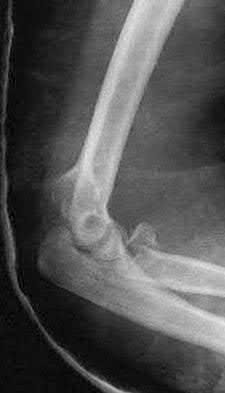

A 24-year-old woman is thrown from her motorcycle and sustains the closed injury shown in Figures A through C. Open reduction and internal fixation is planned. What surgical technique will best allow visualization of the joint surface and allow early range of motion?

Access to complex intra-articular fractures is best achieved by an olecranon osteotomy (OO). Fixation can be with parallel plating or orthogonal plating.

Bicolumnar fixation of distal humerus fractures should follow the principles outlined by O'Driscoll: Distal fragments should be held by as many screws as possible; every screw in the distal fragments should pass through a plate; each screw should engage as many articular fragments as possible.

Galano et al. review treatment for bicolumnar distal humerus fractures. They note that the olecranon osteotomy, Alonso-Llames triceps sparing and Campbell triceps splitting approaches expose 57%, 46% and 35% of the articular surface, respectively. The OO and paratricipital (triceps sparing)

approaches allow for early ROM. Protected motion is required for the O'Driscoll TRAP and Bryan-Morrey approaches for tendon-to-bone healing.

Coles et al. retrospectively reviewed the OO in fixation of 70 fractures. Osteotomy fixation was with an intramedullary screw and dorsal ulnar wiring, or with a plate. The rate of OO increased with fracture difficulty (from AO type C1-C3). There was 1 delayed union but no nonunions.

Figures A and B show a AO/OTA type C2 intraarticular distal humerus fracture. Figure C is a coronal CT scan showing intraarticular comminution. Illustration A shows fixation of the fracture with bicolumnar plating through an olecranon osteotomy approach. Illustration B shows the various approaches to the distal humerus (left, Campbell triceps splitting; center left, O'Driscoll triceps reflecting anconeus pedicle; center right, Bryan-Morrey approach, leaving the triceps attached laterally to the fasciocutaneous flap, but elevating it off the ulna; right, olecranon osteotomy). Illustration C shows 3 methods of olecranon osteotomy (A and B, Intra-articular transverse; C-F, Extra-articular oblique; G, Intra-articular chevron).